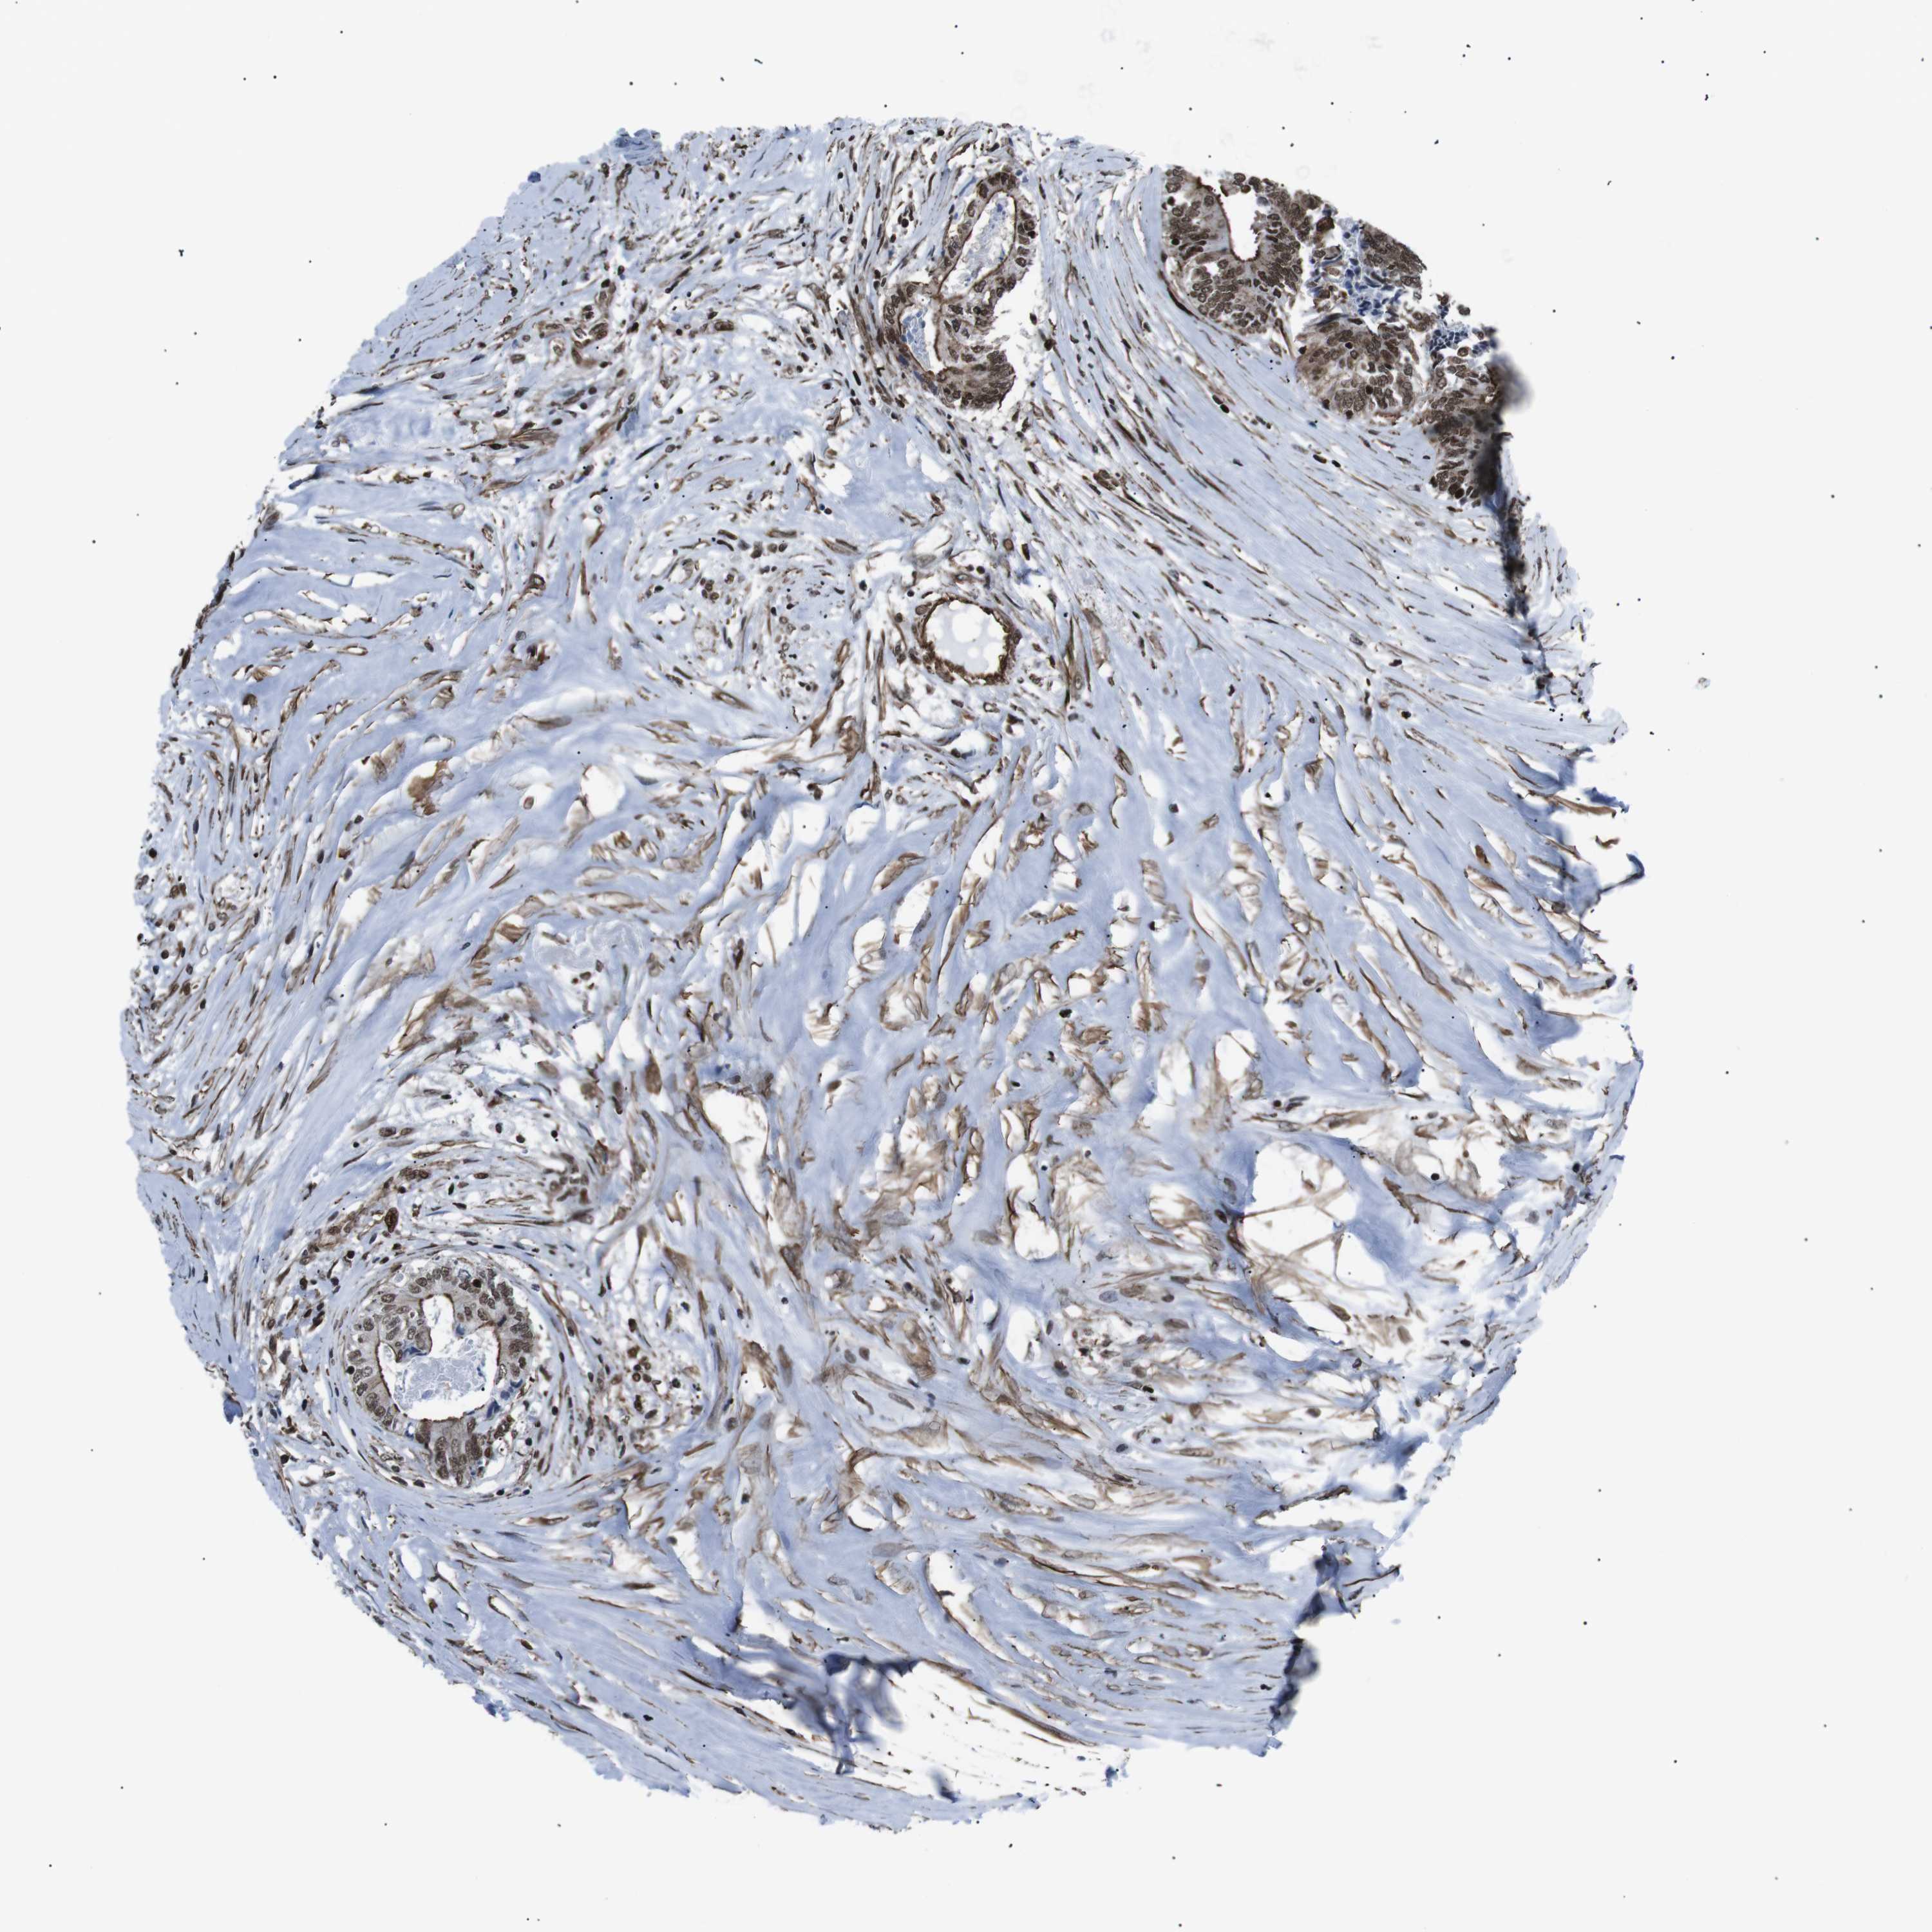

Colorectal cancer

Rectum adenocarcinoma